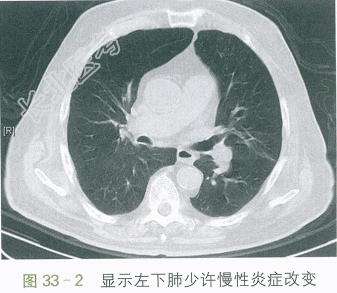

胸部平扫CT:肺气肿,两肺少量慢性为主炎症。如图33-1、图33-2所示。